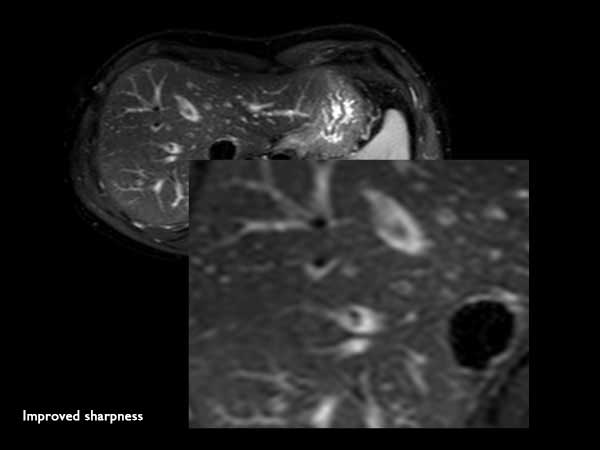

Axial Diffusion (b1200)

Axial Diffusion (b1200) SENSE = 2.5 in AP direction

Axial Diffusion (b1200) SENSE = 4 in RL direction